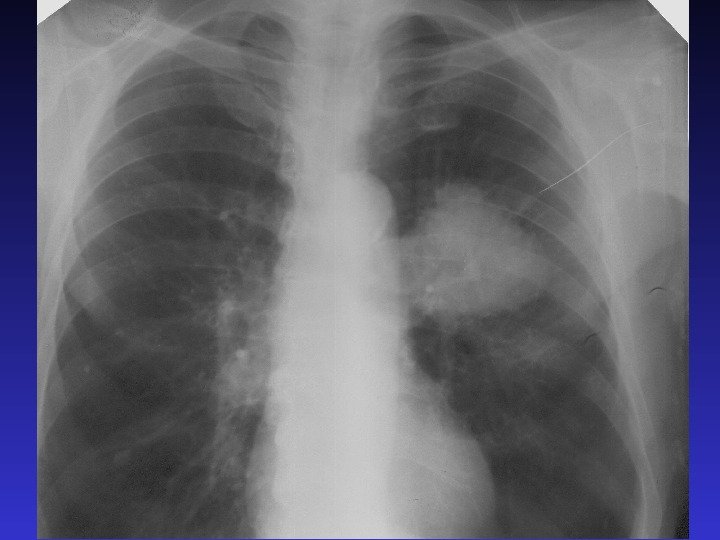

РЕНТГЕНОГРАФИЯ ОРГАНОВ ГРУДНОЙ КЛЕТКИ В прямой проекции В боковой проекции Легкие – обширные участкиРЕНТГЕНОГРАФИЯ ОРГАНОВ ГРУДНОЙ КЛЕТКИ В прямой проекции В боковой проекции Легкие – обширные участки просветления, на фоне которых определяются линейные тени (легочный рисунок).

Характеристика затемнения 1.  Локализация (поля, зоны, ребра, доли,  сегменты) 2. Протяженность (тотальное,Характеристика затемнения 1. Локализация (поля, зоны, ребра, доли, сегменты) 2. Протяженность (тотальное, субтотальное, ограниченное) 3. Интенсивность (высокая, средняя, низкая – эталон сосуды или ребра) 4. Структура (однородная, неоднородная) 5. Форма (округлая, треугольная и т. п. ) 6. Характер контуров (четкие, нечеткие)

Протяженность затемнения 1. Тотальное  - все 3 легочных поля 2.  Субтотальное Протяженность затемнения 1. Тотальное — все 3 легочных поля 2. Субтотальное — 1 -2 легочных поля

ТОТАЛЬНОЕ ЗАТЕМНЕНИЕ Причины частые: ателектаз, жидкость в плевральной полости, наличие инфильтрации  Редкие причины:ТОТАЛЬНОЕ ЗАТЕМНЕНИЕ Причины частые: ателектаз, жидкость в плевральной полости, наличие инфильтрации Редкие причины: отек, цирроз, фиброторакс, опухоль, занимающая гемиторакс

СУБТОТАЛЬНОЕ ЗАТЕМНЕНИЕ ПРИЧИНЫ: ателектаз, жидкость в плевральной полости,  воспалительная инфильтрация,  отек, цирроз,СУБТОТАЛЬНОЕ ЗАТЕМНЕНИЕ ПРИЧИНЫ: ателектаз, жидкость в плевральной полости, воспалительная инфильтрация, отек, цирроз, опухоль.